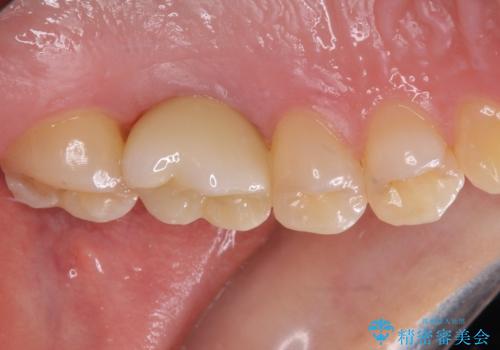

- 抜歯が必要と診断された奥歯を気にして来院された患者様です。

抜歯の上インプラントによる補綴治療を行うこととなりましたが、前歯の叢生も気になるとのことで並行して矯正治療を行うこととしました。

痛みがないので、ボロボロのまま放置していましたが、抜歯後は汚れが溜まりにくくなりスッキリとしたようです。

前歯のデコボコも解消され、ブラッシングが楽になりました。